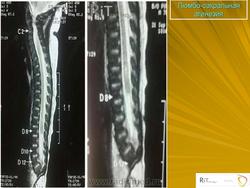

Видела люмбосакральную агенезию в 30 лет, кт обп+мт по поводу мкб. Могу кадров накидать.

Парень инвалид-колясочник, полностью сохранен в остальном и очень позитивен.

обещанное